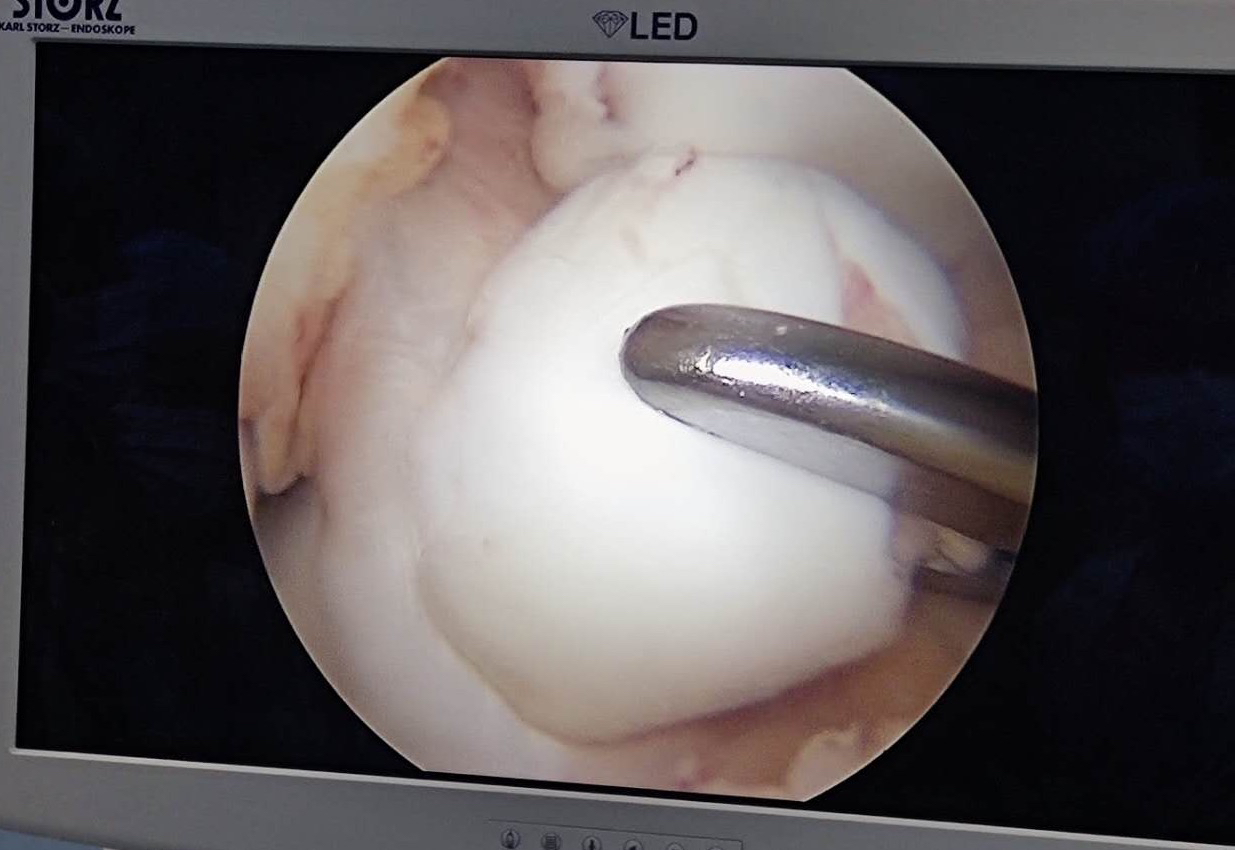

髌骨脱位造成髌骨内下极骨软骨骨折 需要CT检查 可以看见关节内游离骨片 (这是绝对需要早期手术的!)